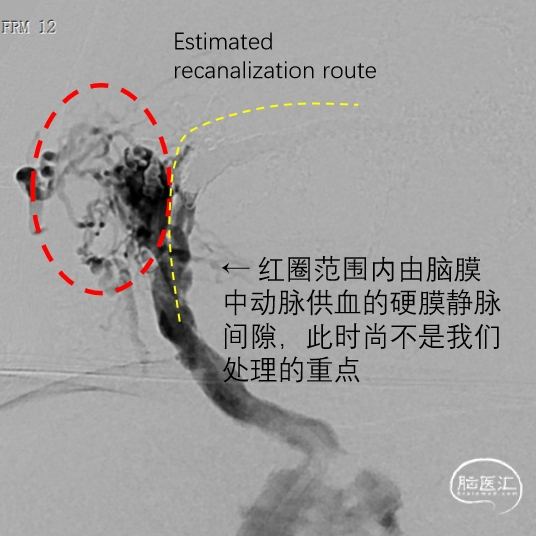

通过静脉窦直接造影,可以将右侧横-乙交界区的窦前共同静脉端进一步分解为两部分:

外侧静脉腔隙(红圈)由颈外动脉分支主要参与供血, 可以通过脑膜中动脉入路闭塞,技术难度最低。

内侧静脉腔隙(黄色虚线)通过脑膜后动脉供血,如果经通过脑膜中动脉,则需要静脉窦大球囊保护,增加Onyx胶沿球囊闭塞功能引流静脉或向动脉端危险返流的风险。